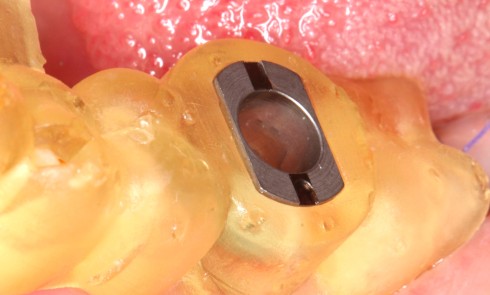

Le terme dysfonctionnement temporo-mandibulaire (DTM) englobe une trentaine de troubles musculo-squelettiques (TMS), douloureux ou non, qui impliquent les articulations temporo-mandibulaires...Le concept SSA : indications et mise en œuvre clinique

Très souvent, l’implantation peut être réalisée dans le même temps opératoire que l’extraction, avec des taux de réussite égaux à...Une lecture efficace au service des patients

La mise en œuvre d’un traitement prothétique implique la collecte de données biologiques (fonctionnelles et esthétiques), afin de créer une...Vidéos